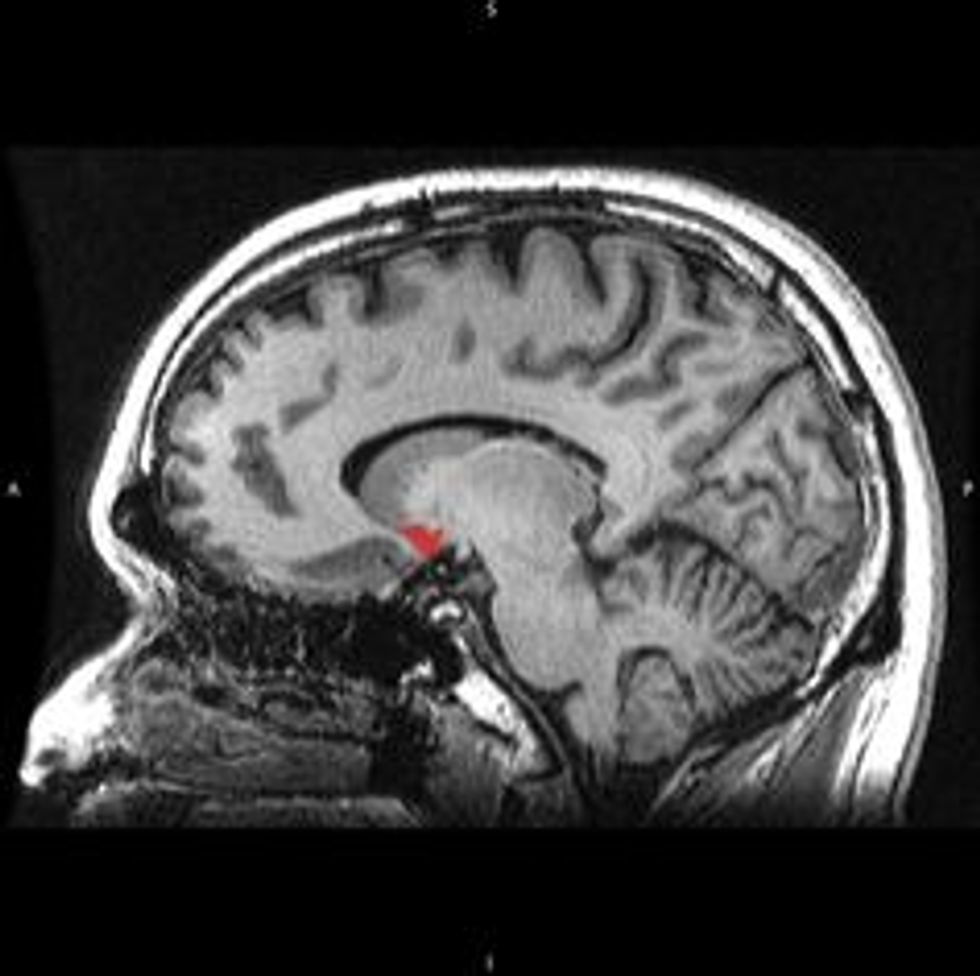

Evolution has resulted in the mesolimbic pathway, a brain system that deciphers these natural rewards for us. When we do something pleasurable, a bundle of neurons called the ventral tegmental area uses the neurotransmitter dopamine to signal to a part of the brain called the nucleus accumbens. The connection between the nucleus accumbens and our prefrontal cortex dictates our motor movement, such as deciding whether or not to taking another bite of that delicious chocolate cake. The prefrontal cortex also activates hormones that tell our body: “Hey, this cake is really good. And I’m going to remember that for the future.”